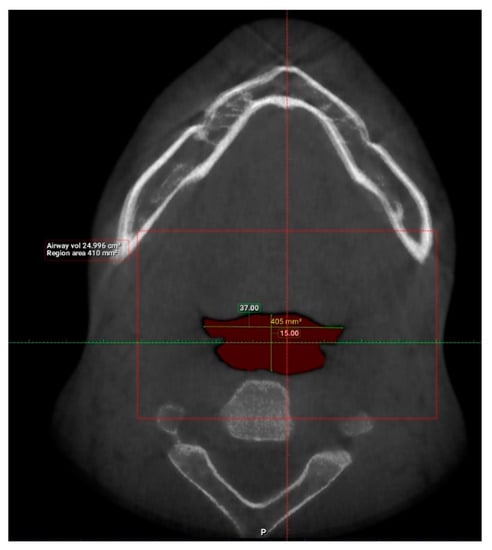

| Total volume (cm3) | 101 | 94.58 | 173.45 | 131.67 | 17.91 |

| Width (mm) | 101 | 8.00 | 37.00 | 21.69 | 6.54 |